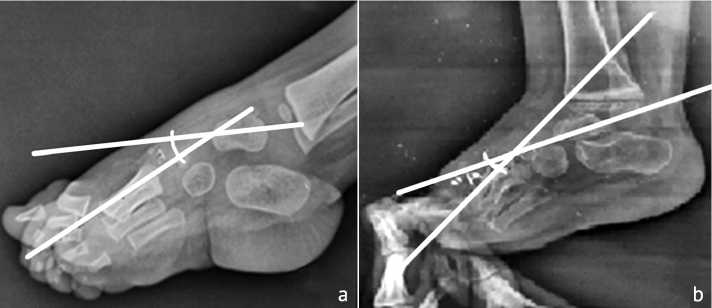

Talus-first metatarsal Angle (AP view) evaluates the alignment and structure of the midfoot and forefoot. It assesses medial-lateral alignment. The angle is formed between the long axis of the talus and the long axis of the first metatarsal. It is 0 to 20º in normal foot; any angle more than this range will consider forefoot adduction (Fig. 3).

Fig. 3. Talo-first metatarsal angle (AP view): (a) classic view; (b) stress view

Talo-first metatarsal angle (lateral view) assesses the longitudinal arch of the foot and the vertical alignment of the talus with the first metatarsal. It evaluates the degree of arch collapse or elevation. The normal value is 0 to 4º (Fig. 4).

Fig. 4. Talo-first metatarsal angle (lateral view): (a) classic view; (b) stress view